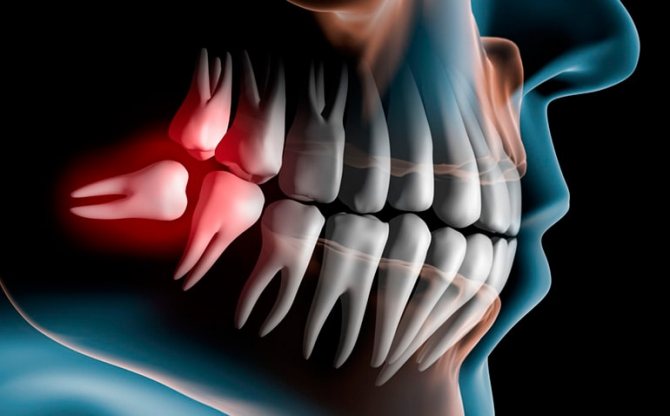

Отдельной категорией проходят зубы мудрости, которые ряд стоматологов рекомендует удалять в срочном порядке, а другие врачи предлагают попытаться сохранить их, даже пойдя на некоторый риск развития осложнений.

- Появление так называемого зуба мудрости. Есть люди, которые ощущают дискомфорт из-за него, тогда этот зубик удаляют.